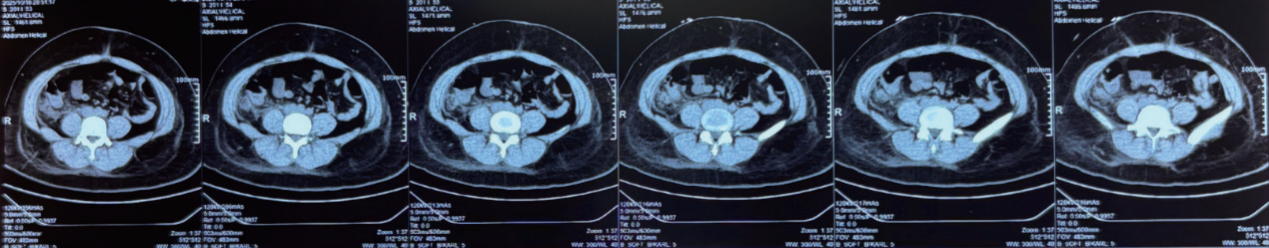

患者在医院船完成腹部 CT 检查,提示占位为腹膜后囊性病变,大小约 18 cm×10 cm,上缘达肝脏下缘,下缘至右髂窝,升结肠等脏器被严重推挤移位(图1)。医院船随即启动多学科会诊,指出患者手术指征明确,但肿瘤体积巨大、位置深在,与周围重要血管及器官关系密切,麻醉与手术风险较高。医疗队同步与汤加维奥拉医院密切协作,提前备妥血制品,应对术中可能的大出血风险,最终制定 “全身麻醉下腹腔镜探查 + 肿瘤切除术(备开腹)” 的治疗方案。

image.png

图1 术前腹部CT